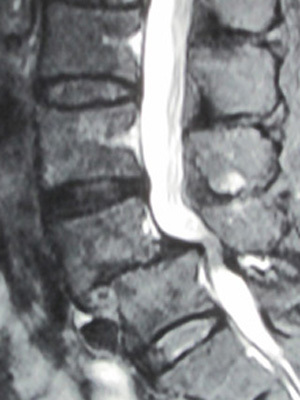

• 腰部脊柱管狭窄症

脊柱管は背中の中央を貫く[神経の通り道]です。

この脊柱管が腰の所で何らかの原因で狭くなり中を通っている神経が圧迫されることによって腰痛やシビレを起こします。

特徴的な症状は[間欠性跛行]で、歩いているうちに足に痛みやシビレが出て歩きにくくなりますがしゃがんだり座ったりすると症状が無くなりまた歩けるのが特徴です。

• 腰痛分離・すべり症

腰痛すべり症とは椎骨が前方にずれた状態で腰痛すべり症と腰椎分離すべり症がある。

主な症状は坐骨神経痛や間欠性跛行である。